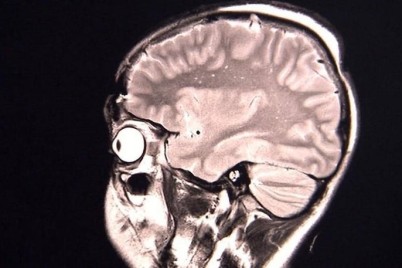

كشف استشاري علاج الأورام بالأشعة الدكتور هدير مصطفى مير، أن هناك بعض الأمور التي يجب أن تتبعها السيدات عند إجراء...

أكد استشاري جراحة التجميل بمستشفى رعاية الوطني الدكتور خالد الفرا أن عملية شفط الدهون هي عملية جراحية تستخدم أسلوب الشفط...

جدة _ ريفان هوساوي نجح فريق طبي من قسم جراحة العيون بمستشفى شرق جدة في إجراء جراحة لمقيمة محوله من...